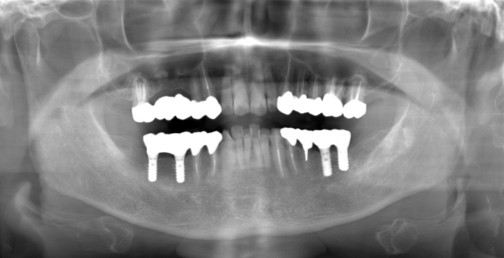

症例1

Before

After

主訴 | 奥歯で噛めるようになりたい |

|---|---|

治療内容 | 下顎の複数本の奥歯をインプラントにて再建 |

治療期間 | 6ヵ月 |

費用 | 200万円 |

副作用・リスク | ・術後に患部に腫れや痛み、違和感などが生じることがあります。 |